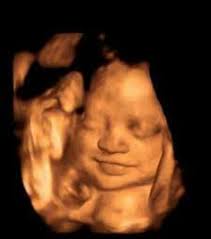

Ecografía 4D

Ecografía 4D/Doppler

Imágenes en tiempo real. Ecografías obstétricas 4D, vasculares Doppler y estudios de partes blandas.

• Imágenes en alta definición

• Grabación de video 4D

• Sin radiación ionizante